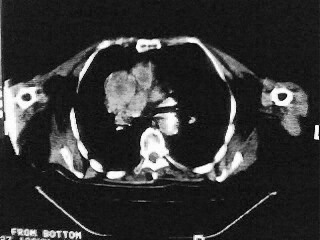

女,79,咳 嗽月余,无其它不适

后纵隔内左心房至肝左叶后方椎体中线偏左巨大软组织包块,其壁均匀比较薄,其内可见宽气液平。

考虑食管裂孔疝。建议钡餐检查